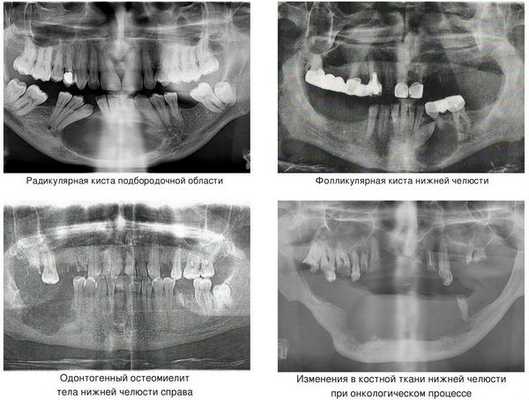

Наиболее частой причиной возникновения перелома нижней челюсти является травматический фактор. В ряде случаев речь может идти о патологическом переломе из-за деструктивных процессов в костной ткани. [1] К таким патологическим процессам относятся:

- кисты челюстей;

- остеомиелит (гнойное воспаление костных тканей);

- онкологический процесс.

Кисты челюстей в основной массе протекают бессимптомно, медленно, но верно разрешая костную ткань. Часто патологический перелом вызвают радикулярные (корневые) и фолликулярные кисты. [2] Первые связаны с изменениями в периапикальных тканях одного или нескольких зубов, вторые являются результатом нарушения прорезывания зубов, чаще нижних зубов мудрости.

При онкологическом процессе нижняя челюсть может быть как первичным очагом, так и местом метастазирования посредством либо прорастания из близлежащих областей, либо распространением с током крови или лимфы. [3] Патологический процесс распространяется до тех пор, пока не разрушит костную ткань нижней челюсти до той стадии, в которой обычное пережевывание пищи может перевести к перелому.